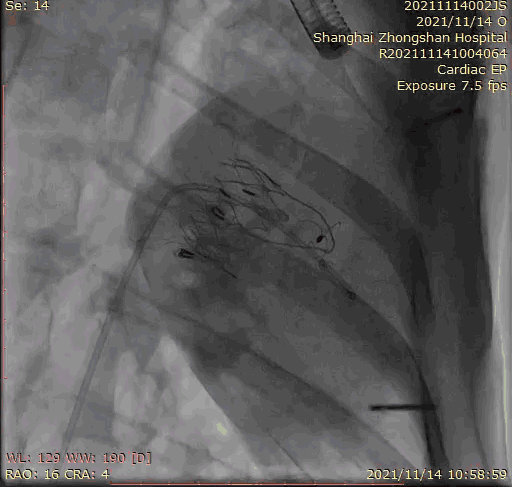

本次臨床前研究經(jīng)右側頸靜脈置入LuX-Valve Plus輸送系統(tǒng)可調彎鞘管,在DSA及超聲引導下將人工三尖瓣瓣膜植入到原有三尖瓣位置,利用獨特的錨定技術將人工瓣膜支架可靠固定在預定的位置。

上海中山醫(yī)院葛均波院士、錢菊英院長、周達新教授、潘文志教授、潘翠珍教授、李偉教授共同完成此次臨床前研究。術后葛均波院士對Lux-Valve Plus的器械操作性能給予了高度評價,DSA和超聲影像也顯示出在本次研究中Lux-Valve Plus的安全性和有效性俱佳。